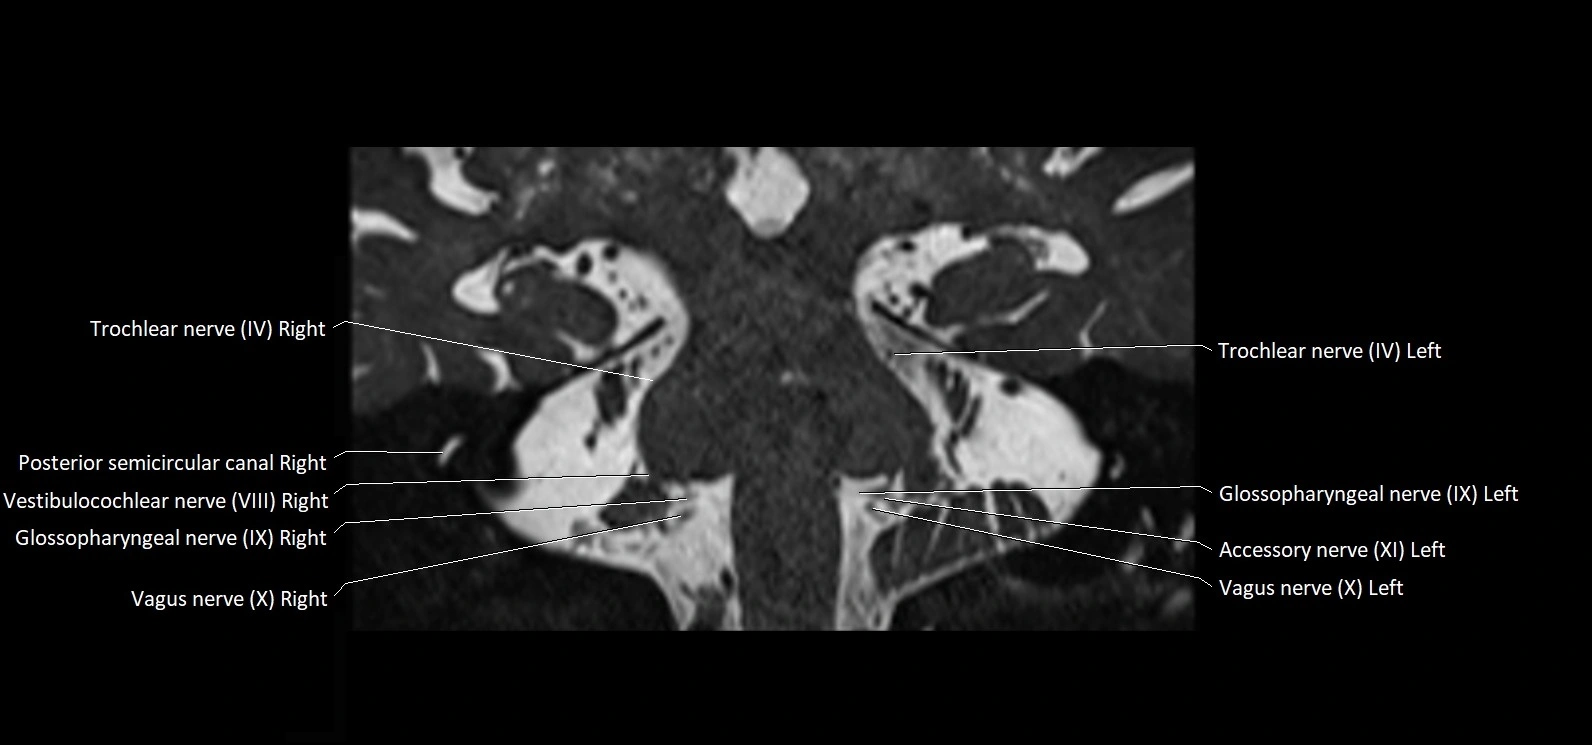

MRI Appearance

• The abducens nerve is a small, thin, linear structure

• Best visualized on high-resolution T2-weighted 3D MRI sequences (e.g., FIESTA or CISS)

• Seen as a hypointense (dark) line running from the brainstem at the pontomedullary junction, traversing the prepontine cistern, and entering Dorello’s canal under the petrosphenoidal ligament, then into the cavernous sinus, and finally the orbit

• May be challenging to visualize in standard MRI due to its small size

• Pathology may be inferred by absence, displacement, or enhancement of the nerve